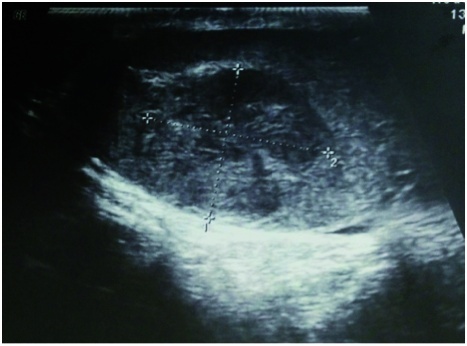

Fallbeispiel: Seminomatöser Hodentumor mit kontralateraler testikulärer intraepithelialer Neoplasie als Zufallsbefund In unserer urologischen Ambulanz (Bundeswehrkrankenhaus Ulm) stellte sich ein 28-jähriger Patient zur Abklärung einer Mikrohämaturie…